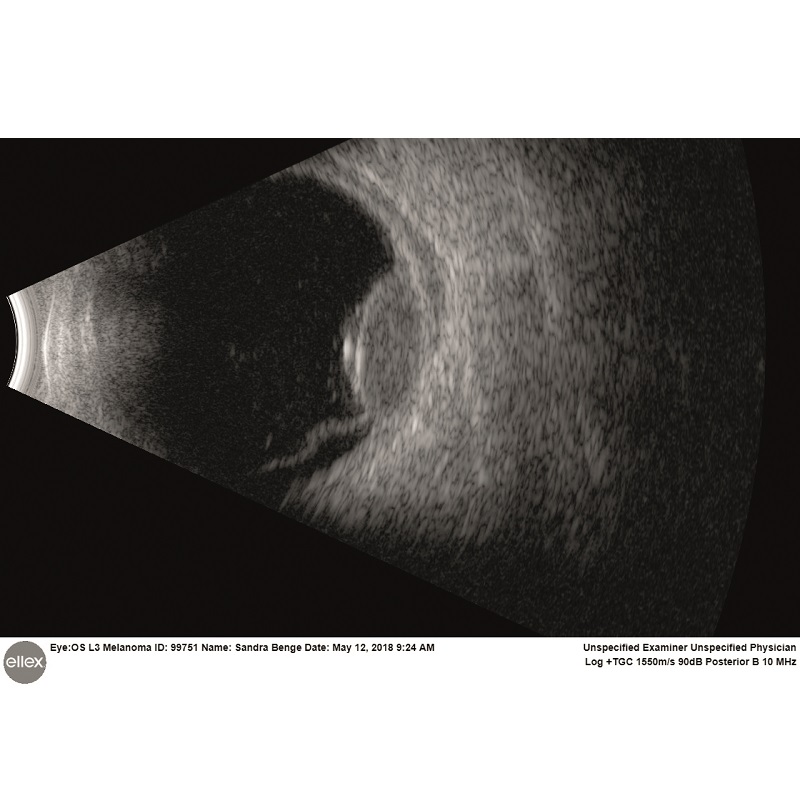

Intuicyjna platforma ultrasonograficzna Eye One obejmuje szeroki zakres trybów skanowania zarówno w odcinku tylnym, jak i przednim. Sprzęt jest w stanie wykryć najsubtelniejsze echa ciała szklistego, oferując niezwykłą dokładność diagnozy siatkówki, naczyniówki czy twardówki. W przednim trybie szerokiego pola Eye One umożliwia oglądanie całego segmentu oka w celu zidentyfikowania przyczyn choroby związanej z jaskrą oraz dokładnego i spójnego pomiaru kluczowych parametrów kąta.

Prezentacja A (tak/nie): Tak

Prezentacja B (tak/nie): Tak

UMB (tak/nie): Tak